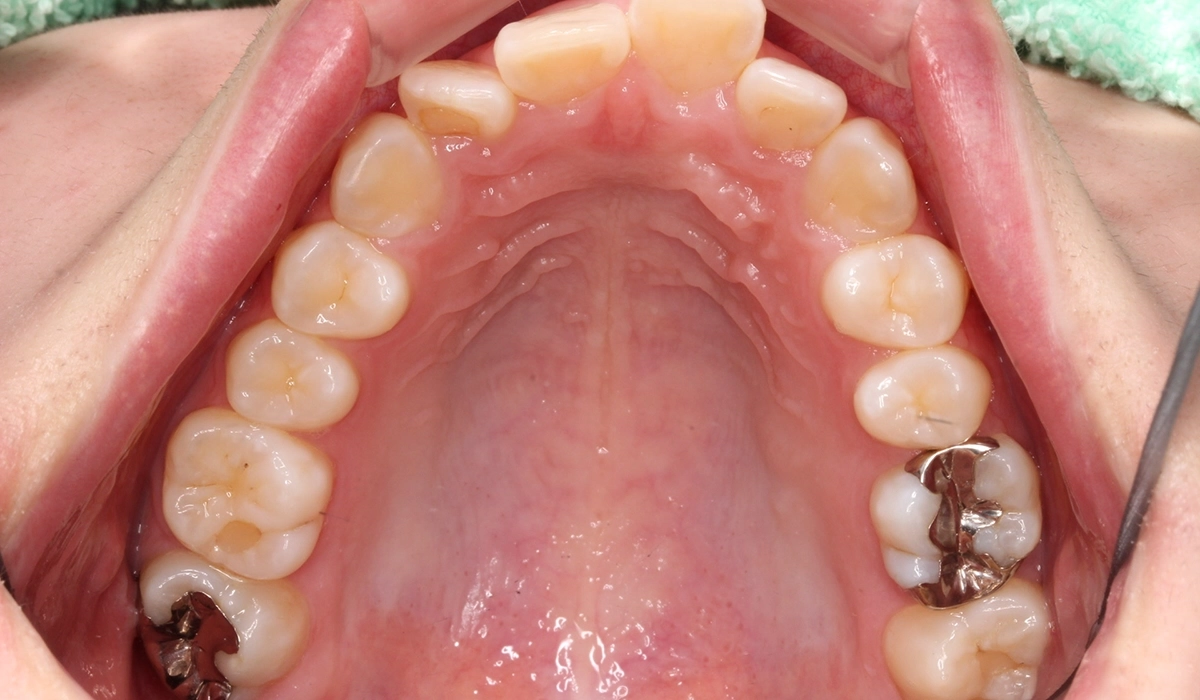

術前:上顎

術後:上顎